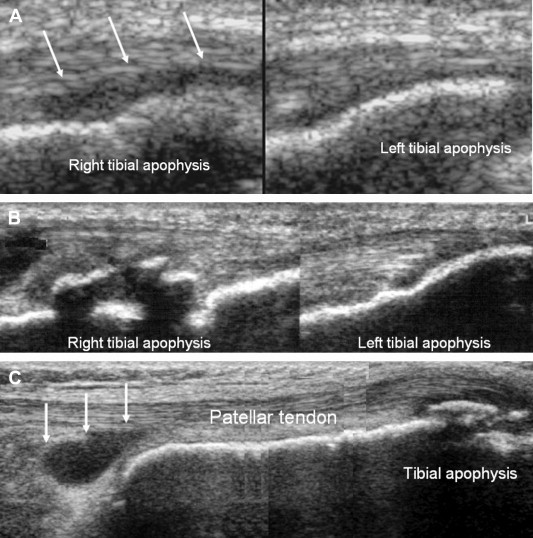

Although there is no universally accepted ultrasound (US) classification of OSD patterns, US is able to detect every pathologic feature and its course such as cartilage swelling, fragmentation of the tibial tubercle ossification center, patellar tendon lesions and reactive bursitis of the deep or superficial tibial patellar bursae [4–6] (Fig. 2).

Fig. 2.

Osgood–Schlatter disease. (A) Comparative sagittal US scans: cartilage swelling can be seen in the right tibial apophysis (arrows); (B) comparative sagittal US scans: fragmentation of the right tibial tubercle ossification center; (C) the sagittal US scan shows reactive bursitis of the deep tibial patellar bursa, besides fragmentation of the tibial tubercle ossification center.